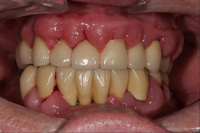

En volymökning av mjukvävnaden kring tänderna som är associerad med intag av läkemedel tillhörande grupperna antiepileptika, immunosuppressiva läkemedel och kalciumblockerare.

Inflammation är den utlösande faktorn som driver tillväxten av mjukvävnaden därför är plackkontroll av största vikt.

Förekomst av gingivala hyperplasier med djupa tandköttsfickor och svåra hygienförhållanden som följd.

Läkemedelsinducerad gingival hyperplasi: